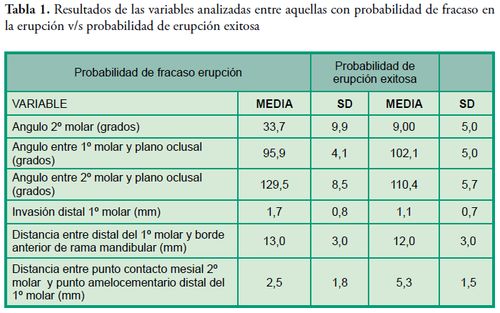

Los pacientes que presentaron probabilidad de fracaso en la erupción corresponden al 1,43% de la muestra, su edad promedio fue de 10 ± 1,7 años, en relación al sexo el 73,3% son mujeres. La variable que se utilizó para determinar la probabilidad de éxito o fracaso en la erupción fue el ángulo del segundo molar: -menor o igual a 24° se consideró probabilidad de erupción exitosa, mientras que -un ángulo de 25° o más se consideró con probabilidad de fracaso en la erupción de acuerdo al promedio manifestado por Evans en 1988 (promedio de 25° con un rango entre 15° a 65°). Las Tablas 1, 2 y 3 expresan los resultados de las variables indagadas y su relación con la probabilidad o no de erupción, la presentación en forma uni o bilateral y su distribución por cuadrante.

Los pacientes que presentaron probabilidad de fracaso en la erupción corresponden al 1,43% de la muestra, su edad promedio fue de 10 ± 1,7 años, en relación al sexo el 73,3% son mujeres. La variable que se utilizó para determinar la probabilidad de éxito o fracaso en la erupción fue el ángulo del segundo molar: -menor o igual a 24° se consideró probabilidad de erupción exitosa, mientras que -un ángulo de 25° o más se consideró con probabilidad de fracaso en la erupción de acuerdo al promedio manifestado por Evans en 1988 (promedio de 25° con un rango entre 15° a 65°). Las Tablas 1, 2 y 3 expresan los resultados de las variables indagadas y su relación con la probabilidad o no de erupción, la presentación en forma uni o bilateral y su distribución por cuadrante.